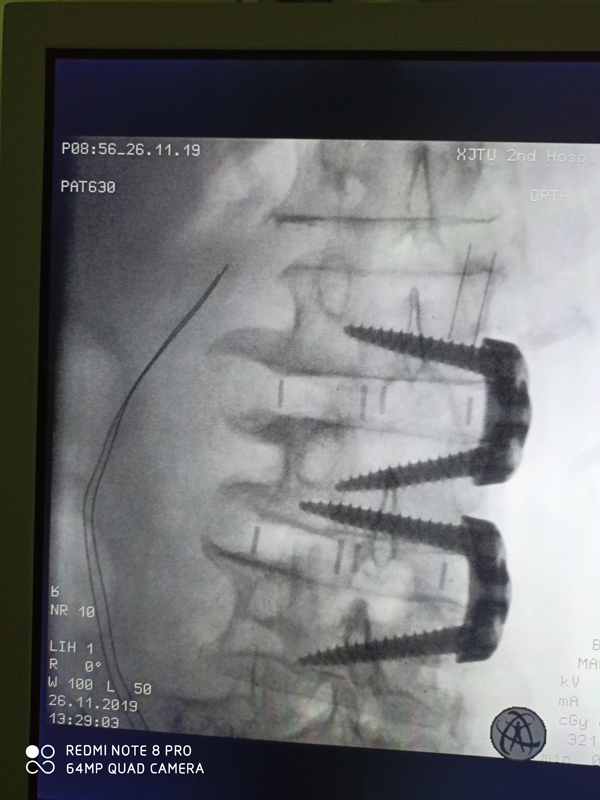

近日,骨一科柏传毅教授团队在党哓谦主任指导下,麻醉科张珍妮教授和手术室护士配合下成功开展医院首例腰椎侧前方微创椎体间融合术(OLIF)。患者为81岁高龄老年女性,腰部间断疼痛数十年,进半年出现腰痛左下肢麻木伴疼痛,患者系高龄患者,骨质疏松、腰椎退行性侧弯,身体耐受性较差,考虑传统腰椎手术失血过多、手术创伤大,术中风险高,经过党哓谦主任组织科室讨论后,决定采用国际前沿的脊柱微创OLIF术式进行治疗。

传统手术,采用腰背部正中切口,切断脊柱附着的肌肉,而且需要切除整个腰椎椎板,而且由于老年脊柱退变变形,存在损伤神经根和硬脊膜的风险,手术时间长、出血量大、并发症多、术后下地时间晚,术后软组织创伤后遗腰痛。考虑到患者属于高龄患者,全身耐受性较差,柏传毅教授团队经过严谨、专业地评估后,决定给患者实施OLIF术式,OLIF是近来国际上流行的一种新型微创腰椎融合手术方式,与传统腰椎手术在背后开刀不同,它是从腹部侧前方的小切口,一般4-5cm就可以完成3个节段的腰椎椎间融合,而且不需要切断肌肉,全部是在肌肉间隙进入的,一个节段手术出血大概30-50ml,和传统后路手术比较创伤小,没有软组织损伤,下地早,后遗症少,同时,OLIF技术直接对腰椎间隙进行松解和撑开,对脊柱畸形有很好的矫正作用,可以缩短手术固定的节段。

手术当日,在麻醉科和手术室配合下,手术顺利完成,术后第二天患者术前下肢疼痛麻木症状消失,下肢活动良好,术后第三天已经可以在保护下下地活动。